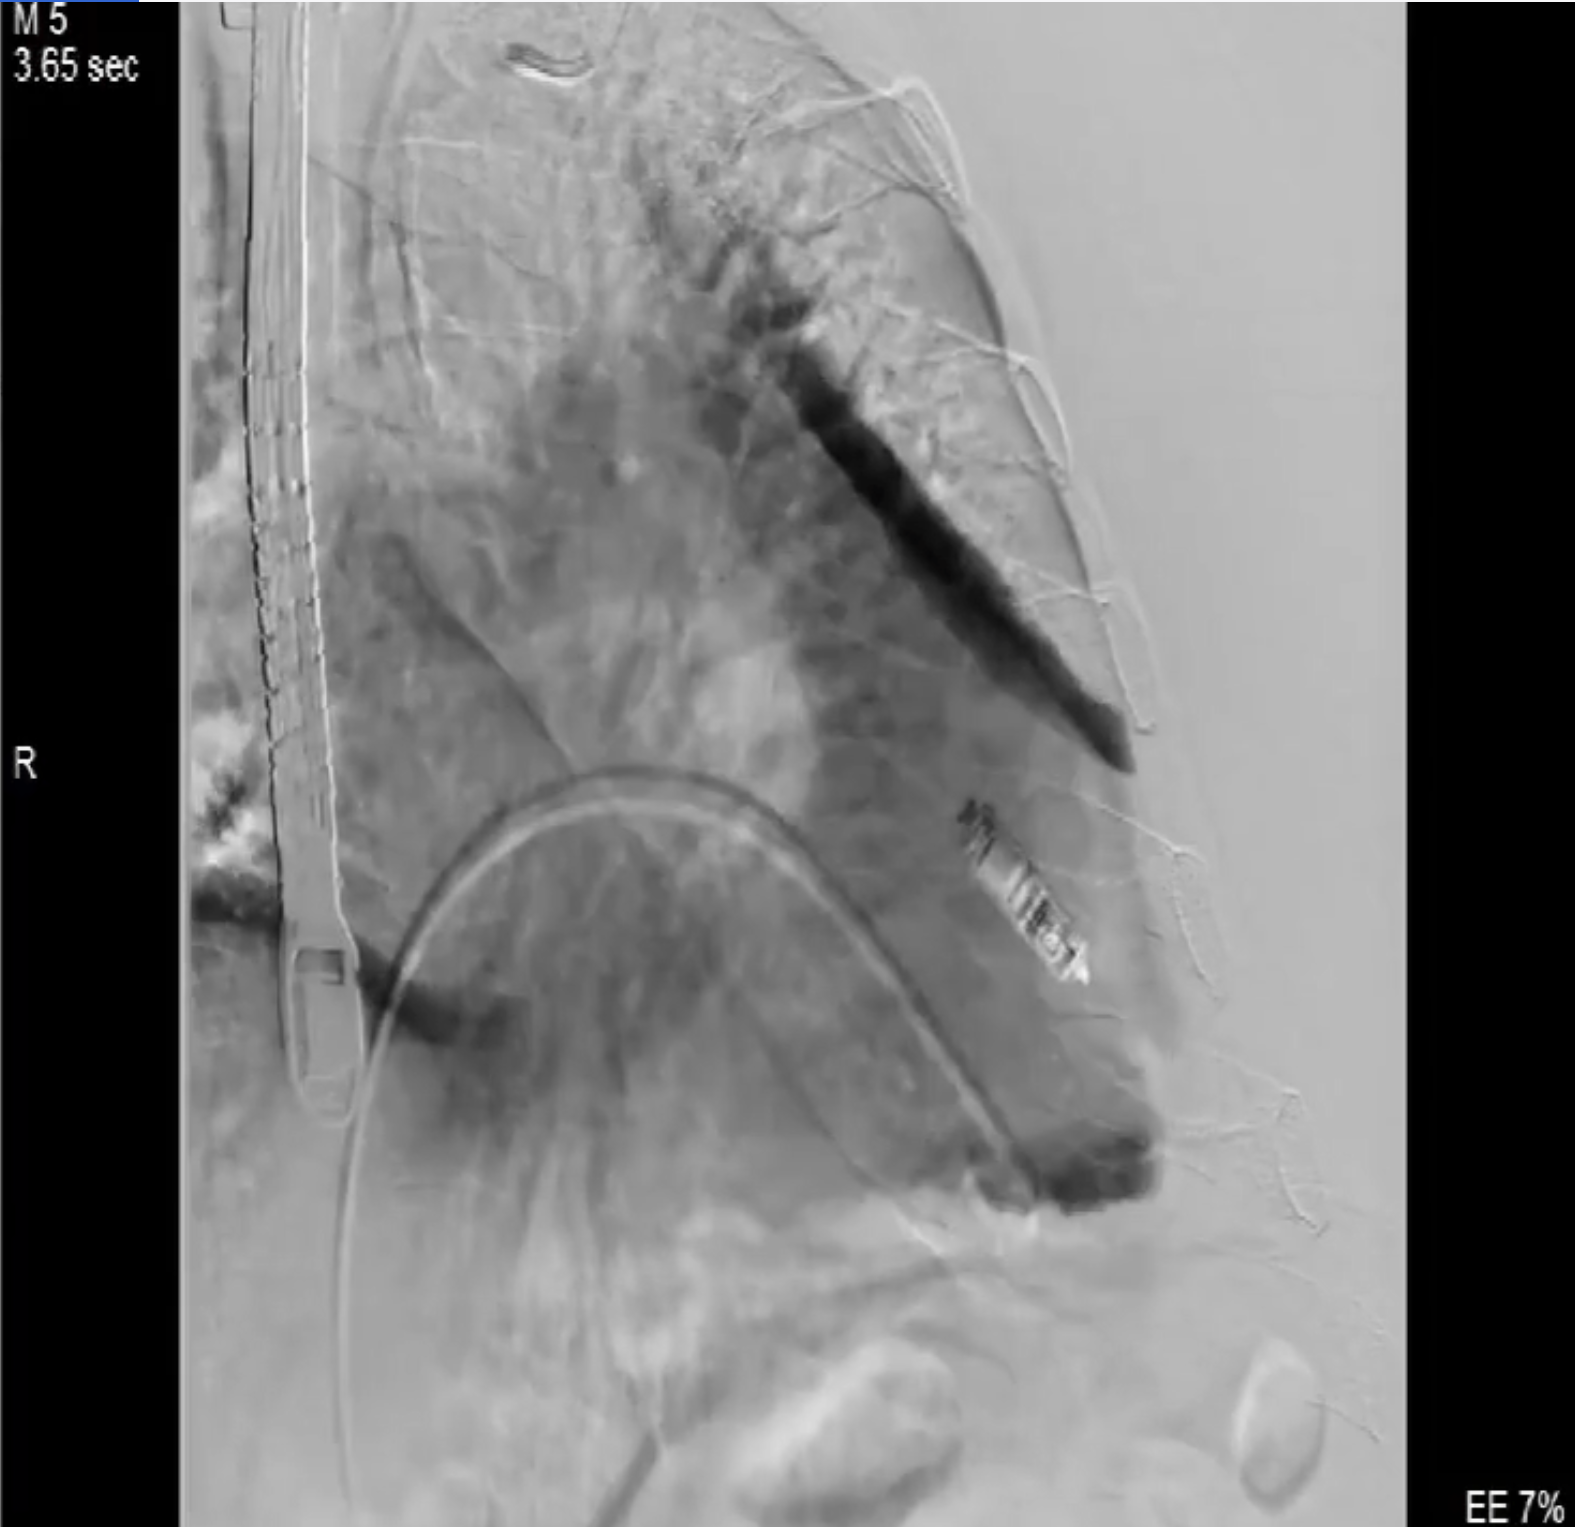

術(shù)中影像

術(shù)前DSA造影可見(jiàn)三尖瓣大量返流呈瀑布樣,右室偏間隔側(cè)可見(jiàn)無(wú)導(dǎo)線(xiàn)起搏器一枚。

本次直播手術(shù)中,手術(shù)團(tuán)隊(duì)在超聲與DSA等多維影像手段的支持下,精準(zhǔn)嫻熟的完成LuX-Valve Plus瓣膜的植入,器械操作時(shí)間僅為30分鐘,瓣膜植入后術(shù)中即刻三尖瓣返流消失,多普勒超聲下無(wú)明顯瓣周漏或中心性返流,肺動(dòng)脈壓正常,平均跨瓣壓差僅為1mmHg,人工瓣膜運(yùn)動(dòng)正常,術(shù)后1小時(shí)內(nèi)該患者即安返病房。